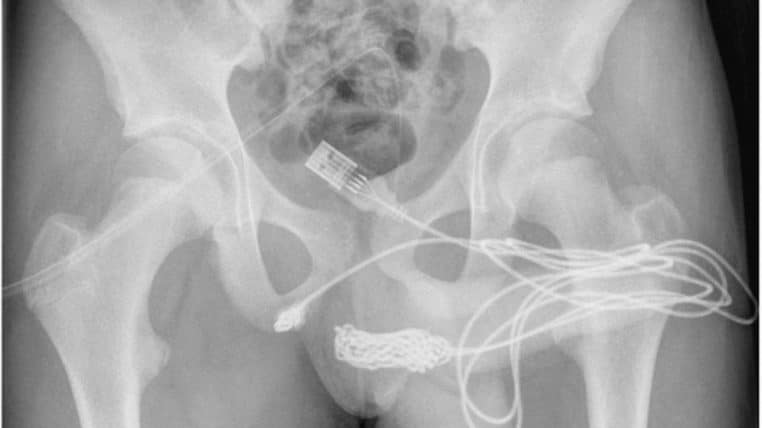

Un adolescent de 15 ans voulait mesurer son pénis avec un câble USB

Au Royaume-Uni, un adolescent de 15 ans s’est introduit un câble USB dans l’urètre pour mesurer la taille de son pénis. Le jeune garçon n’est pas parvenu à le retirer lui-même et a donc dû être pris en charge à l’hôpital. Le fil s’était emmêlé à l’intérieur de son sexe.

L’adolescent a dû être opéré pour extraire le câble USB. Selon les médecins, le cas d’insertion de corps étrangers dans l’urètre est « une rareté clinique ». Le garçon va mieux et ne présente pas de séquelles.